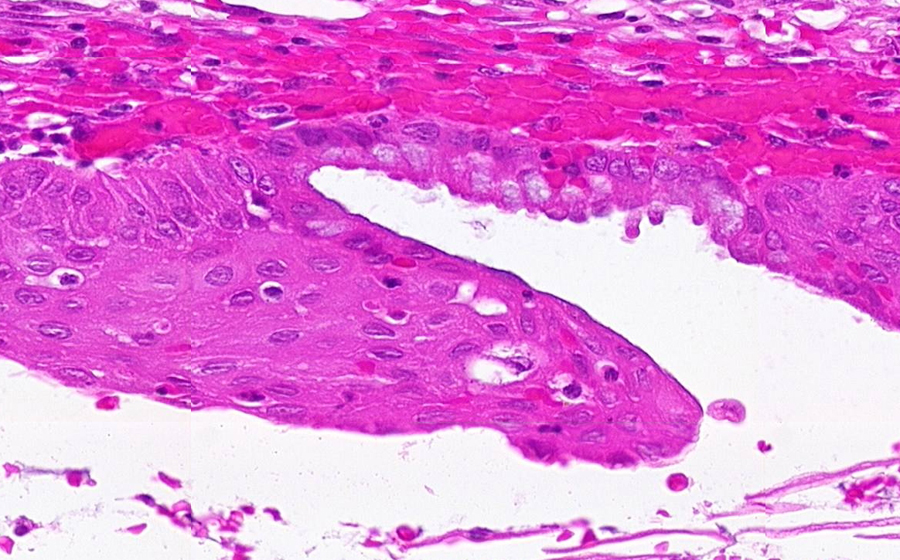

Slide 3: Chronic cervicitis and metaplasia

Histologic section of cervix from a patient with chronic cervicitis (click here to review normal tissue)

Image 3 - 100X

Slide 3 - Image 3